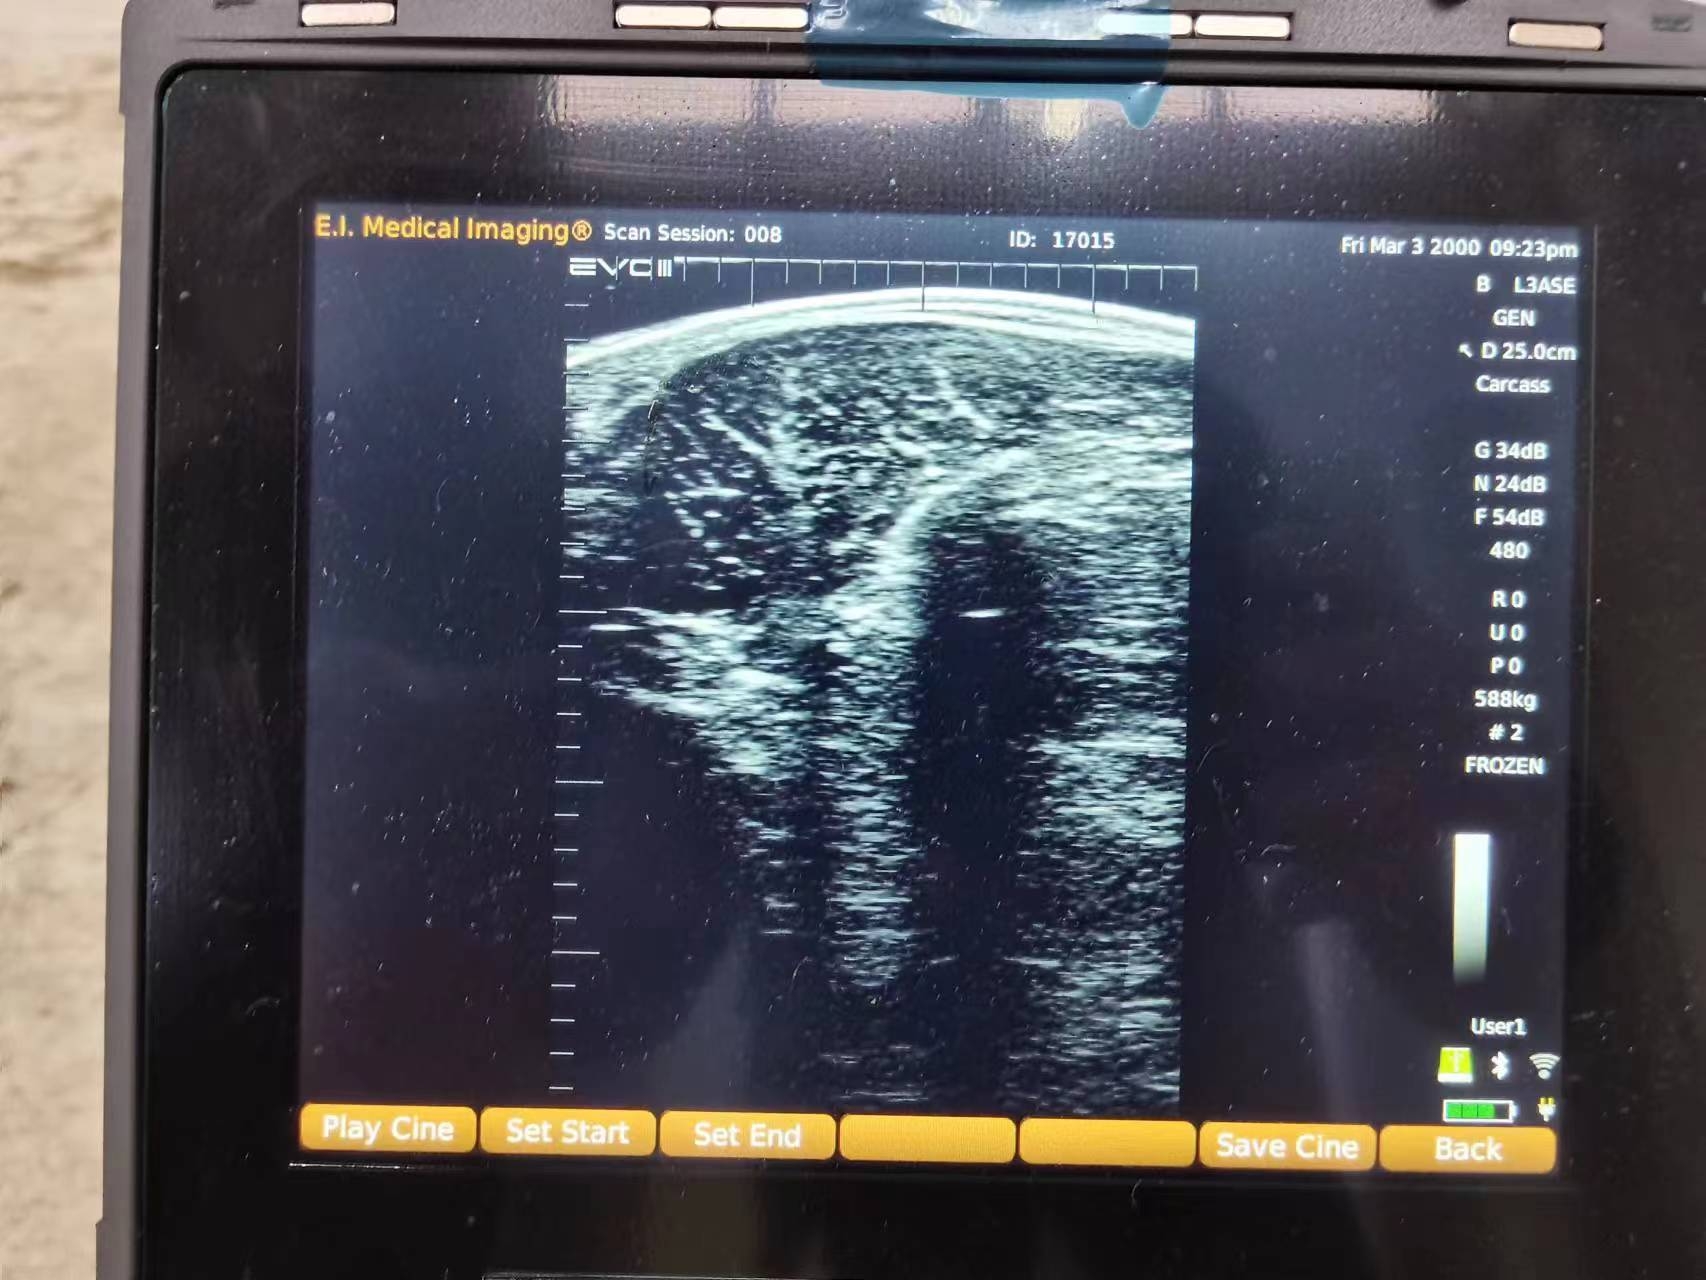

与传统检测方式不同,智能AI肉牛育种B超机不仅能够获取清晰的超声影像,还可以通过智能算法对背膘厚度、眼肌面积以及肌内脂肪相关参数进行自动识别与测量。这种从“看影像”到“读数据”的转变,大幅降低了人为经验差异带来的误判,让检测结果更加稳定可靠。

在养殖实践中,背膘厚度是反映肉牛能量利用和脂肪沉积水平的重要指标。借助智能AI测量功能,养殖人员可以快速获得标准化的背膘数据,并进行阶段性对比,从而更科学地调整日粮结构,避免过肥或营养不足对肉质和饲料成本造成影响。

眼肌面积作为衡量瘦肉产量和生长潜力的重要遗传参数,通过智能AI算法自动识别后,可形成可存储、可分析的数据记录。这些数据不仅可用于当前育肥管理,也为种牛选留和育种决策提供了长期参考,有助于逐步提升群体遗传水平。

在高品质牛肉生产过程中,肌内脂肪沉积的稳定性尤为关键。智能AI肉牛育种B超机通过对肌肉结构影像的分析,为判断肌内脂肪发展趋势提供了数据支持,使养殖者能够在不同育肥阶段对饲养策略进行更精细的调整,而不再依赖单一经验。